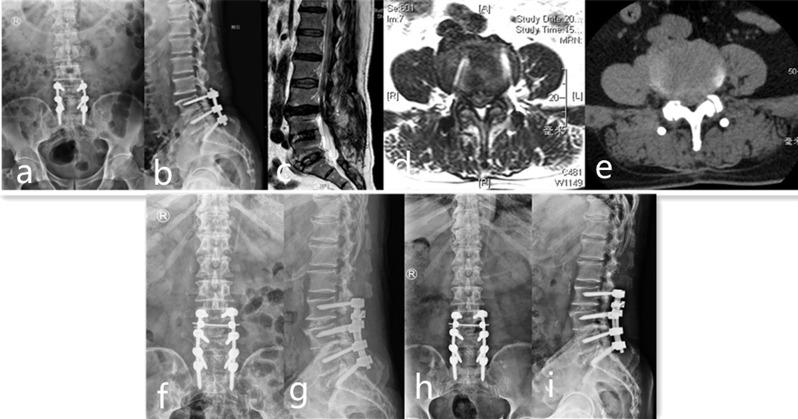

66 patients with symptomatic ASD who failed conservative treatment for more than 1 month and received repeated lumbar surgery were retrospectively collected in the study from January 2015 to November 2018, with the average age of 65.86 ± 11.04 years old. According to the type of surgery they received, all the patients were divided in 2 groups, including 32 patients replaced the prior rod in Group A and 34 patients received PELD at the adjacent level in Group B. Patients were followed up routinely and received clinical and radiological evaluation at 3, 6, 12 months and yearly postoperatively. Complications and hospital costs were recorded through chart reviews.

The majority of patients experienced positive surgical outcomes. However, three cases encountered complications. Notably, Group B patients demonstrated superior pain relief and improved postoperative functional scores throughout the follow-up period, alongside reduced hospital costs (P < 0.05). Additionally, significant reductions in average operative time, blood loss, and hospital stay were observed in Group B (P < 0.05). Notwithstanding these benefits, three patients in Group B experienced disc re-herniation and underwent subsequent revision surgeries.